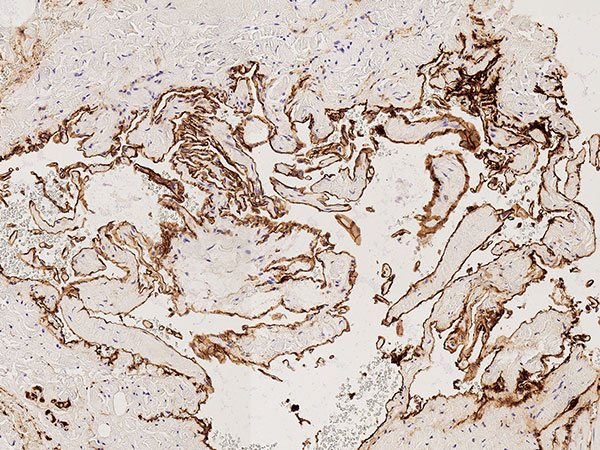

Histopathology, CD31 staining, 110× magnification: Strong staining (dark brown-stained cells) of the entire border of the irregular, vascular dysplastic cavities with the vascular endothelium-specific marker CD31 clearly indicates a vascular malformation. Only a very thin vessel wall is detectable beneath the vascular endothelium.